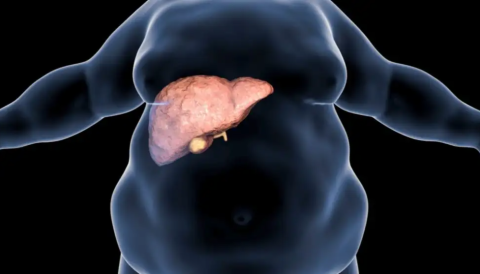

Un problema silencioso avanza en el mundo y preocupa cada vez más a la comunidad médica. Se trata de una condición vinculada a la acumulación de grasa en el hígado, generalmente asociada a factores metabólicos como la obesidad y la diabetes tipo 2. Aunque suele no presentar síntomas en sus primeras etapas, puede evolucionar hacia complicaciones graves.

Los investigadores advierten que este crecimiento está directamente relacionado con el aumento global del sobrepeso, la diabetes y el sedentarismo. Además, factores como la glucosa elevada en sangre y el tabaquismo también contribuyen al deterioro de la salud hepática.

Especialistas señalan que el impacto ya se refleja en un incremento de enfermedades graves, como el cáncer hepático y la necesidad de trasplantes. De no implementarse políticas públicas efectivas, las consecuencias podrían afectar la calidad de vida a nivel global.